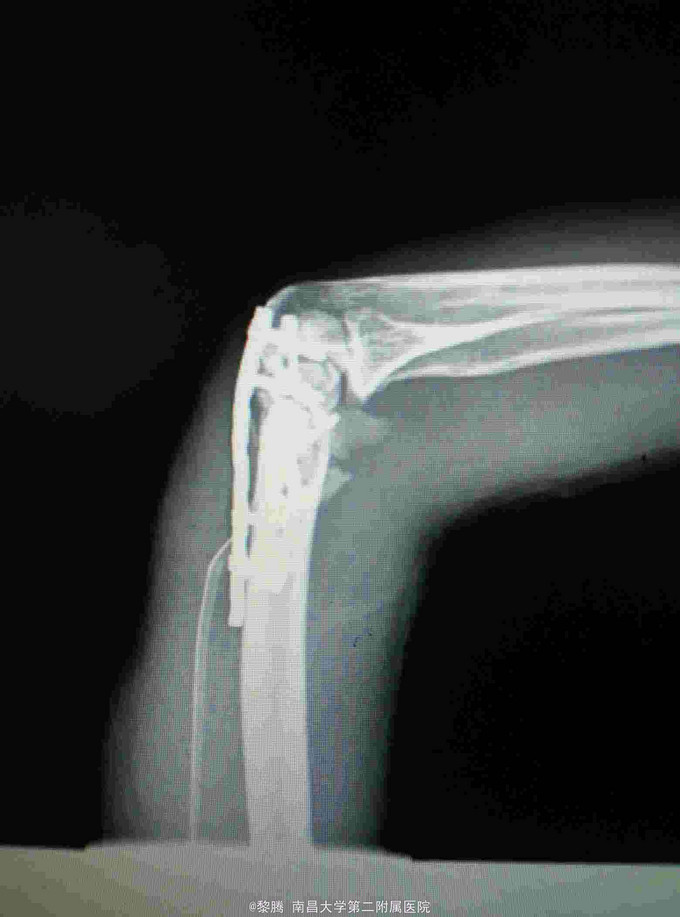

诊断:左肱骨髁间粉碎性骨折 治疗:骨折切开复位内固定+尺神经前置术

随访:患者术后4天出院,左肘关节伸屈活动较前明显好转。术后定期复查。 讨论:患者未予鹰嘴截骨入路亦有较好视野暴露,一般情况粉碎性肱骨髁间骨折,截骨能提供良好暴露,便于操作。患者术中应先找到尺神经并保护,随后进行后续操作。要注意术后功能锻炼,这样才有机会恢复肘关节活动度。